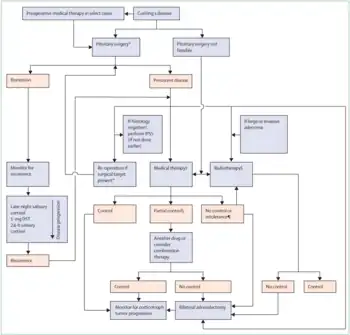

Diagnosis

ACTH=adrenocorticotropic hormone.

CBG=corticosteroid-binding globulin.

CRH=corticotropin-releasing hormone.

DST=dexamethasone suppression test.

IPSS=inferior petrosal sinus sampling.

UFC=urinary free cortisol.

*There is consensus that all patients with lesions smaller than 6 mm in diameter should have IPSS and those with lesions of ≥10 mm do not need IPSS, but expert opinions differed for lesions 6–9 mm in diameter.

†This alternative option does not have clear consensus and needs further research, and this is indicated by darker boxes.

Green boxes indicate points to consider

Darker colors indicate less validated testing pathways.

Cushing's syndrome can be ascertained via a variety of tests which include the following:[53]

- 24-hour urine free cortisol

- Dexamethasone suppression test

- Saliva cortisol level

Treatment

Most cases of Cushingoid symptoms are caused by corticosteroid medications, such as those used for asthma, arthritis, eczema and other inflammatory conditions. Consequently, most patients are effectively treated by carefully tapering off (and eventually stopping) the medication that causes the symptoms.

If an adrenal adenoma is identified, it may be removed by surgery. An ACTH-secreting corticotrophic pituitary adenoma should be removed after diagnosis. Regardless of the adenoma's location, most patients require steroid replacement postoperatively at least in the interim, as long-term suppression of pituitary ACTH and normal adrenal tissue does not recover immediately. Clearly, if both adrenals are removed, replacement with hydrocortisone or prednisolone is imperative.

In those patients not suited for or unwilling to undergo surgery, several drugs have been found to inhibit cortisol synthesis (e.g. ketoconazole, metyrapone) but they are of limited efficacy. Mifepristone is a powerful glucocorticoid type II receptor antagonist and, since it does not interfere with normal cortisol homeostasis type I receptor transmission, may be especially useful for treating the cognitive effects of Cushing's syndrome.[54] However, the medication faces considerable controversy due to its use as an abortifacient. In February 2012, the FDA approved mifepristone to control high blood sugar levels (hyperglycemia) in adult patients who are not candidates for surgery, or who did not respond to prior surgery, with the warning that mifepristone should never be used by pregnant women- although pregnancy is extremely rare during the course of Cushing's Syndrome[55][56][57] [58] In March 2020, Isturisa (osilodrostat) oral tablets a 11-beta-hydroxylase enzyme inhibitor was approved by FDA for treating those patients who cannot undergo pituitary surgery or for patients who underwent surgery but continue to have the disease.[59]

DST=dexamethasone suppression test.

IPSS=inferior petrosal sinus sampling.

ACTH=adrenocorticotropic hormone.

*Pituitary surgery should be performed by an experienced surgeon.

†Absence of ACTH-staining adenoma.

‡See table 2 and panel 3 for considerations regarding selection of medical therapy.

§Lifelong monitoring for hypopituitarism and secondary neoplasia in the radiation field required.

¶On maximum tolerated dose of the drug.

Removal of the adrenals in the absence of a known tumor is occasionally performed to eliminate the production of excess cortisol.[60] In some occasions, this removes negative feedback from a previously occult pituitary adenoma, which starts growing rapidly and produces extreme levels of ACTH, leading to hyperpigmentation. This clinical situation is known as Nelson's syndrome.[61]